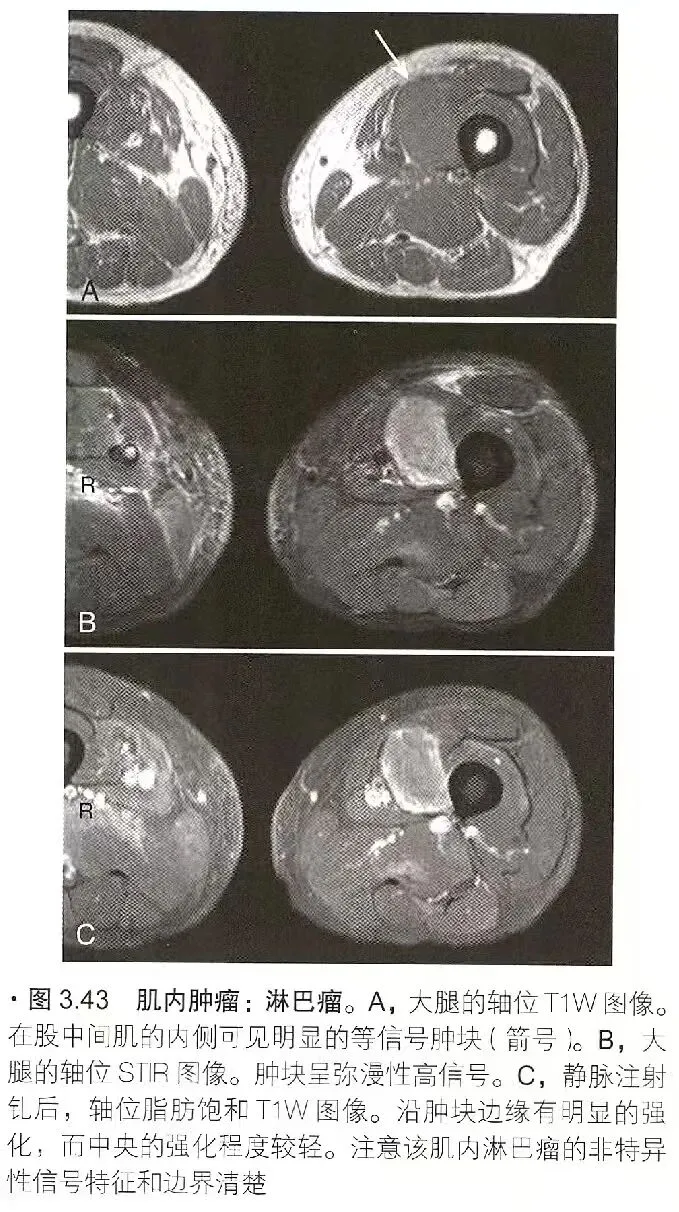

肿瘤